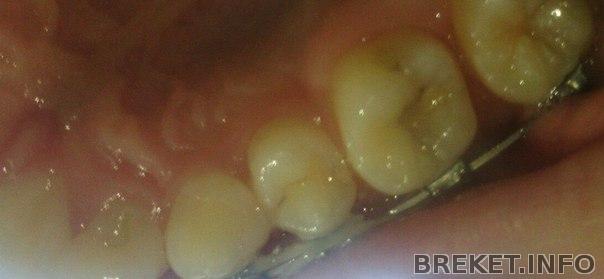

А еще в упор не вижу кариеса,который якобы есть. Тратить 5к на "лечение" здорового зуба не хочется, пусть я и не спец в этом, но по-моему отсутствие кариеса там явно очевидно. Надо будет предложить посмотреть еще раз, на всякий случай.

Что до щелей,то наверное, все же лучше прикрепить сюда фото.Заранее извиняюсь за содержание и качество, ибо изворачиваясь держать два зеркала и камеру -не так просто, да еще и из-за освещения пришлось использовать вспышку.

Но в целом суть ясна, и поэтому, разве такие щели допускают снятие?

Щель огромная! И да, кариес я вижу(

Ну да, щель есть и если то темное пятно-это кариес, то да, он есть

ЮлияHowes,Antigen, нет-нет, предполагаемый кариес совсем на другом зубе,который мне не удалось сфотографировать... а насчет этого, так это пломба, которую в любом случае придется менять.